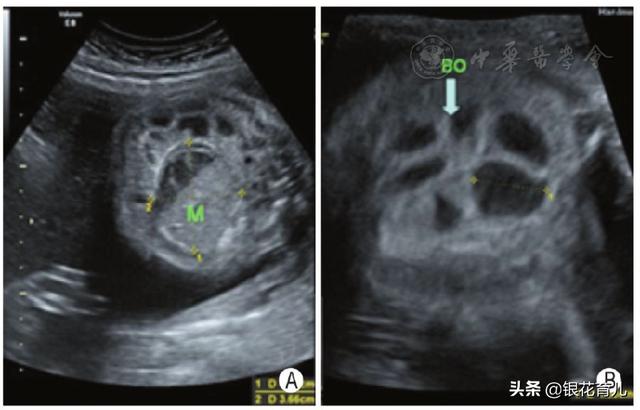

胎粪性腹膜炎是胚胎期由于某些原因造成肠道穿孔,胎粪进入腹腔,引起无菌性、异物性和化学性炎症的结果。

胎儿因肠梗阻阻碍胎儿吞咽羊水的运行,孕妇多伴有羊水过多,X线检查显示胎儿腹腔内有钙化斑块,一般就能确诊。